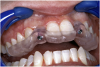

Before the day of surgery, the patient was seen by the orthodontist for the removal of the orthodontic brackets. The patient still was not pleased with the position of the two centrals, and it was determined that this would be addressed after implant placement (Figure 13A). The anatomical variations of the crestal tissue and lack of interdental papilla can be appreciated in the close-up views of the right and left sites (Figure 13B and 13C). There were no surprises on the day of surgery as all of the decisions were made during the planning phase, before the scalpel ever touched the patient. The occlusal view of the CT 3D model revealed the wider alveolar ridge on the right side and thinner crest on the left side (Figure 14A). This was confirmed when the full thickness mucoperiosteal flaps were elevated, and the underyling bone revealed (Figure 14B). The tooth-borne templates were designed to facilitate the drills and drilling sequence specific to the diameters of the predetermined implants (Figure 15A). Each template contained an embedded 5-mm long stainless steel tube, which was approximately 0.2-mm wider than each drill (just wide enough to allow for the drills to rotate freely). Once positioned over the natural teeth, the template was secure and offered precision accuracy in transferring the implant locations from the original software-designed plan, allowing the potential for internal and external irrigation (Figure 15B).

Figure 13a  Before implant surgery, the orthodontic brackets were removed, revealing (A) the position of the centrals, and (B, C) the anatomical variations of the crestal tissue and lack of interdental papilla.

Figure 13a

Figure 13b  Before implant surgery, the orthodontic brackets were removed, revealing (A) the position of the centrals, and (B, C) the anatomical variations of the crestal tissue and lack of interdental papilla.

Figure 13b

Figure 13c  Before implant surgery, the orthodontic brackets were removed, revealing (A) the position of the centrals, and (B, C) the anatomical variations of the crestal tissue and lack of interdental papilla.

Figure 13c